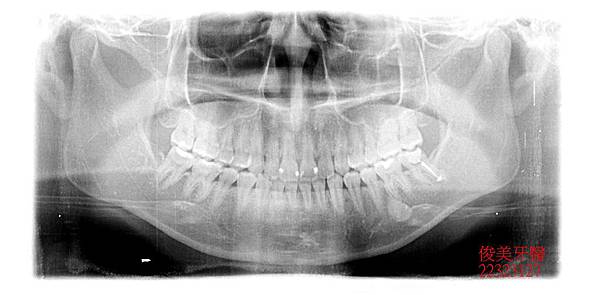

患者為女性,年約25歲,於門診時表示,左下牙齒在其他地方治療後仍會疼痛,於是在搜尋資料後

,找到我們診所,希望可以諮詢醫師的意見;經醫師檢查後發現,左下第二大臼齒根尖有狀況,且

牙齒破損嚴重,加上患者症狀已持續一段時間,此顆牙齒位置及角色重要,但牙齒所剩價值卻不多

,因此建議患者將此顆牙齒拔掉根治。